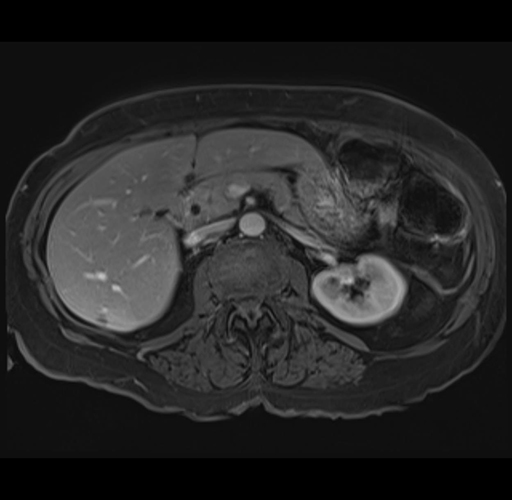

MRI T1

Imaging analysis